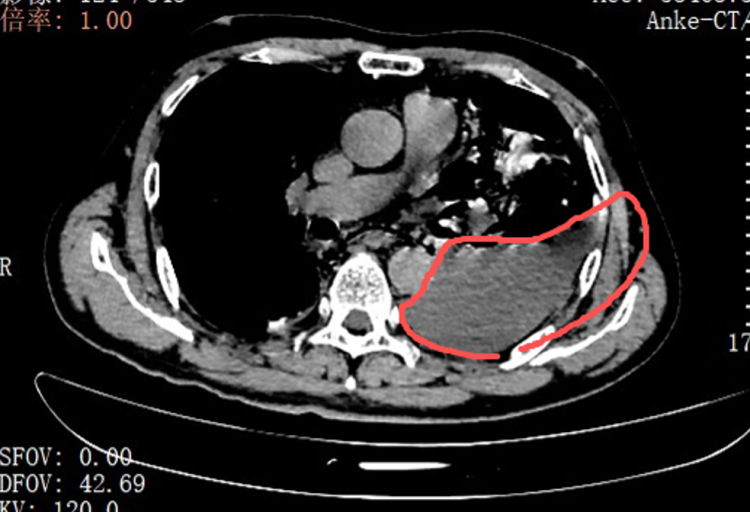

当天,手术团队为张叔实施了胸腔镜下食道修补微创手术。打开胸腔的那一刻,在场的医护人员都愣住了:整个左侧胸腔里,全是叉烧包的菜叶子、食物残渣,混着脓液和消化液,到处都是。

红圈区域是食物残渣、消化液破入食管

手术团队拿着吸引器,一点点清理、冲洗,花了很长时间才将胸腔里的每一点食物残渣都清干净。随后,团队找到了食道下段那道长达10公分的裂口,用可吸收线小心翼翼地完成了分层修补。